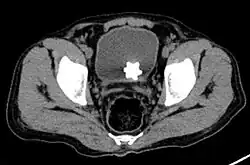

Large jackstone in the bladder of a 60-year-old man. Stone was removed by open cystolithotomy

A star-shaped Jackstone urolith can be seen in the urinary bladder on this radiograph of the pelvis

Jackstone calculi are rare bladder stones that have an appearance resembling toy jacks. They are almost always composed of calcium oxalate dihydrate and consist of a dense central core and radiating spicules. They are typically light brown with dark patches and are usually formed in the urinary bladder and rarely in the upper urinary tract. Their appearance on plain radiographs and computed tomography in human patients is usually easily recognizable. Jackstones often must be removed via cystolithotomy.[10]